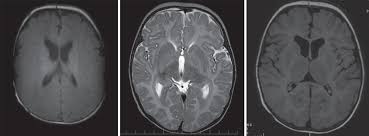

Pre diagnostiku choroby je dôležité neurologické vyšetrenie vrátane zobrazovacieho vyšetrenia CNS - typickou známkou je hypomelinizácia  pri vyšetrení MRI mozgu. Diagnóza v rodine potvrdí molekulárne genetické vyšetrenie.